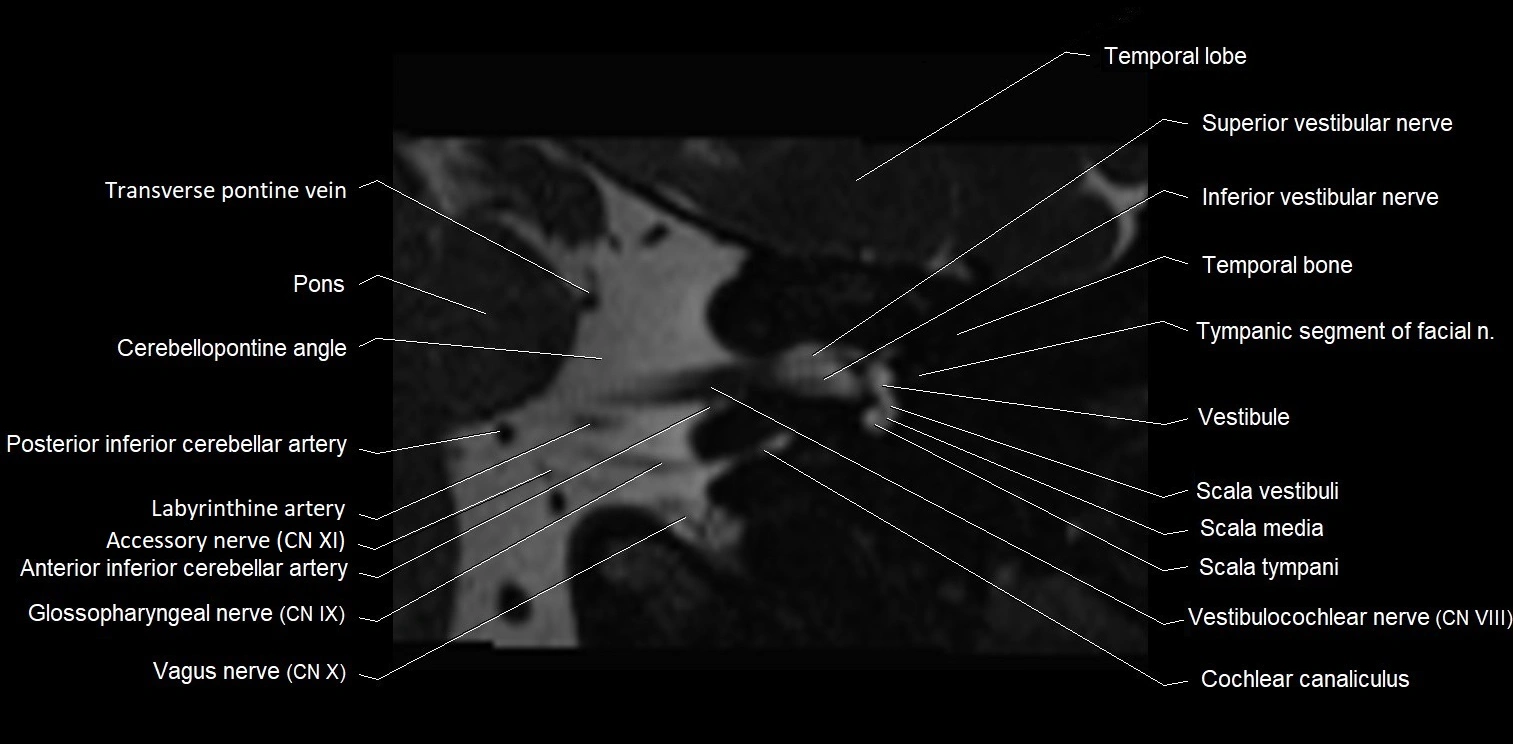

MRI images

image